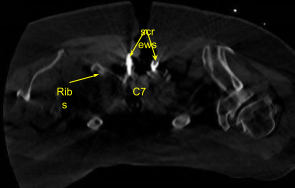

Image-guided stereotactic frame with neuronavigation techniques were used to place the instrumentation. We placed bilateral T1 pedicle screws and decorticated with electric high-speed drill cannulating with the navigated pedicle finder, palpating for breaches, measuring the depths, under tapping by 11 mm and placing 30 mm x 5.0 mm titanium pedicle screws bilaterally without difficulty.

Next, we placed bilateral lateral mass screws at C6. Inspecting the deformity of the spine, a decision was made not to place the C5 lateral mass screws because of kyphotic deformity and difficulty with rod placement.

So, we next decorticated the joints at C6-C7 and C7-T1 and bilateral T1 transverse processes with electric high-speed drill for the arthrodesis. The autograft resected was morselized. Precut-precontoured titanium rods were placed across the tulips from C6 to T1 and secured with locking caps and then final tightened with a torque and anti-torque device.